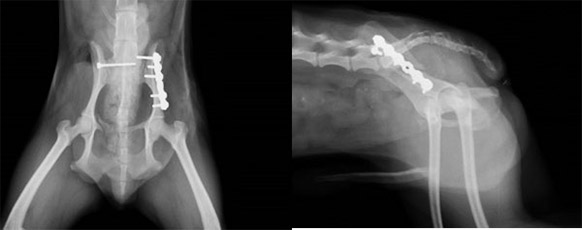

骨盤骨折

手術前:左腸骨体骨折および右仙腸関節脱臼が認められます。

手術後:プレートおよびラグスクリュー固定を行いました。